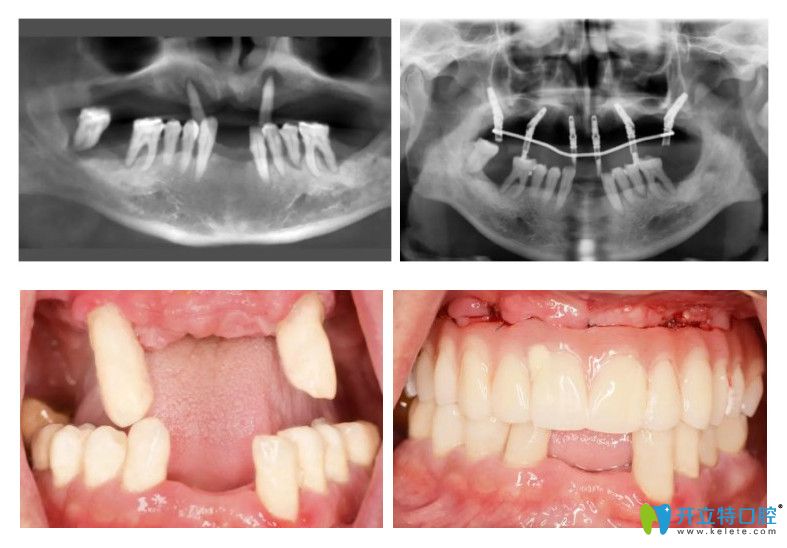

半口種植牙的病例展示:

種植半口牙的病例

60歲的張大爺,得了牙周病,牙齒脫落了很多,由于病例較復(fù)雜,跑了好些口腔醫(yī)院都沒法種植,通過朋友介紹來到圣貝口腔就解決了半口牙齒種植,用了6顆種植體,就恢復(fù)了半口牙齒的咀嚼功能!